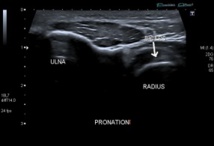

Nous passons donc par voie postérieure, l'avant bras étant positionné en pronation. L'aiguille peut être entrée n'importe où et son trajet sera suivi sur l'écran jusqu'à la cible, les seules structures à franchir étant alors la peau et un plan musculaire.